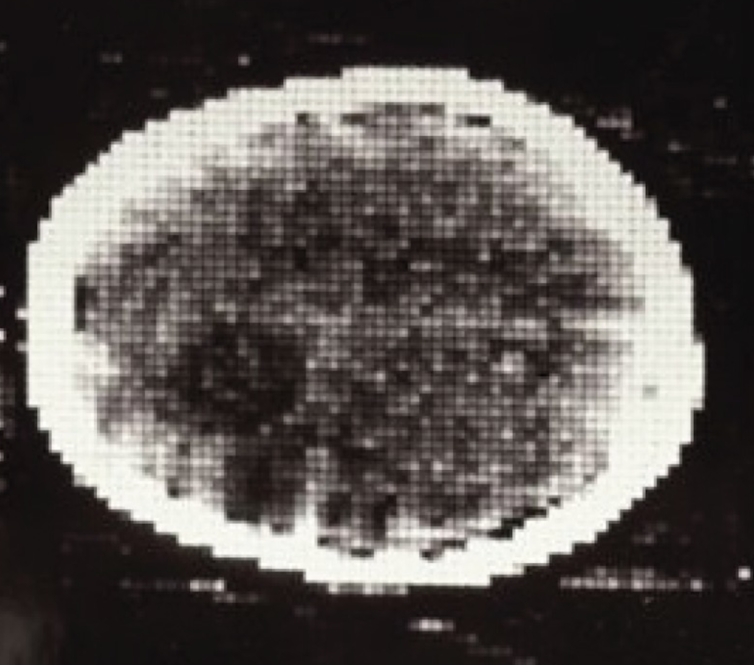

Meanwhile, Hounsfield needed patients to try out his machine on. He found a somewhat reluctant neurologist who agreed to help. The team installed a full-sized scanner at the Atkinson Morley Hospital in London, and on Oct. 1, 1971, they scanned their first patient: a middle-aged woman who showed signs of a brain tumor.

It was not a fast process – 30 minutes for the scan, a drive across town with the magnetic tapes, 2.5 hours processing the data on an EMI mainframe computer and capturing the image with a Polaroid camera before racing back to the hospital.

And there it was – in her left frontal lobe – a cystic mass about the size of a plum. With that, every other method of imaging the brain was obsolete.